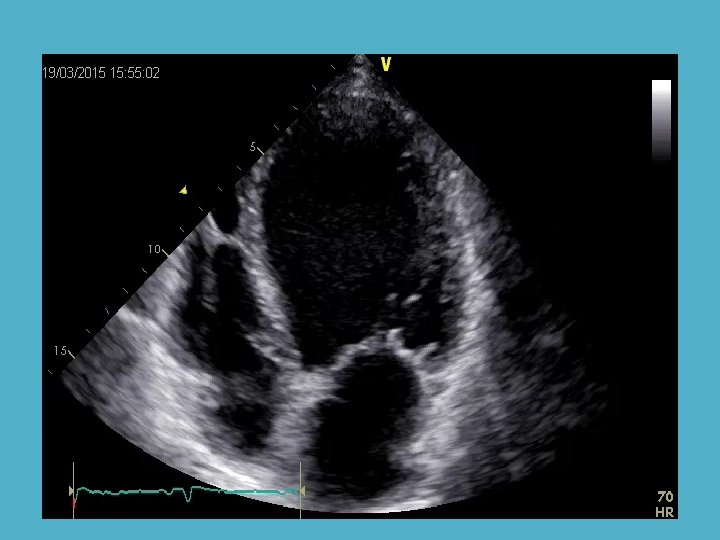

LV EF : 23%